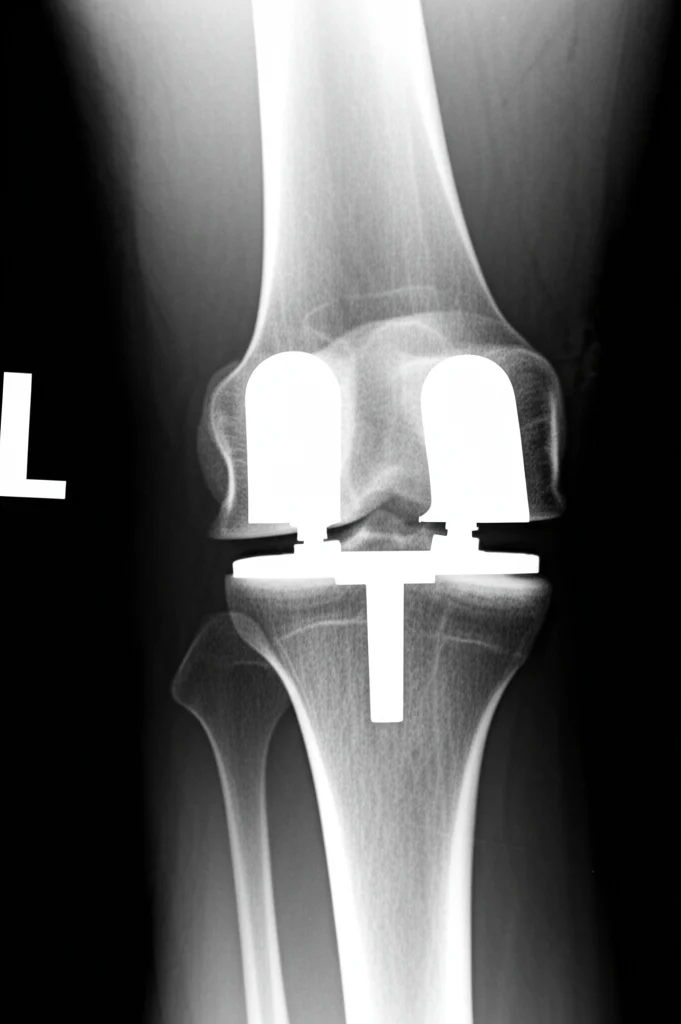

Magro è Bello? Non Sempre in Sala Operatoria: I Rischi Nascosti della Protesi Articolare con Basso BMI

Ciao a tutti! Oggi voglio parlarvi di un argomento che, ammettiamolo, spesso passa in secondo piano quando si discute di interventi di protesi articolare, come quella all’anca o al ginocchio. Siamo bombardati di informazioni sui rischi legati all’obesità e al sovrappeso in questi casi, ed è giusto che sia così. Ma vi siete mai chiesti cosa succede all’estremo opposto? Cosa comporta essere troppo magri quando si deve affrontare un’operazione così importante?

Istintivamente, potremmo pensare: “Meno peso, meno stress sull’articolazione nuova, tutto più facile!”. Beh, la realtà, come spesso accade in medicina, è un po’ più complessa e sfumata. Avere un indice di massa corporea (BMI) basso, a volte considerato un vantaggio in altri contesti, potrebbe nascondere delle insidie non da poco nel percorso chirurgico e post-operatorio dell’artroplastica.

Lo studio canadese ha seguito per anni (fino a oltre 12 anni in alcuni casi!) ben 1.162 pazienti operati di protesi d’anca o ginocchio, primarie o di revisione, che rientravano in queste categorie di BMI (< 25 kg/m²). Di questi, circa il 16% aveva un BMI basso (< 20). I ricercatori hanno analizzato principalmente due cose: il rischio di dover subire un nuovo intervento chirurgico (reoperazione) sulla stessa articolazione e il rischio di andare incontro a complicazioni composite (un mix di problemi come dolore persistente oltre i 6 mesi, problemi di guarigione della ferita, o segni radiografici di fallimento dell’impianto, lussazione, frattura).